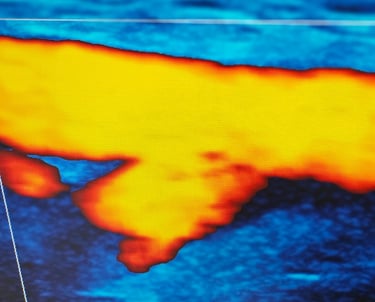

ECODOPPLER DE VASOS DEL CUELLO

También llamado doppler carotídeo, es un estudio que evalúa el sistema arterial del cuello, arterias carótidas, subclavia, vertebrales, para la detección de patologías arteriales fundamentalmente la detección de placas lipídicas, frecuente causa de acv